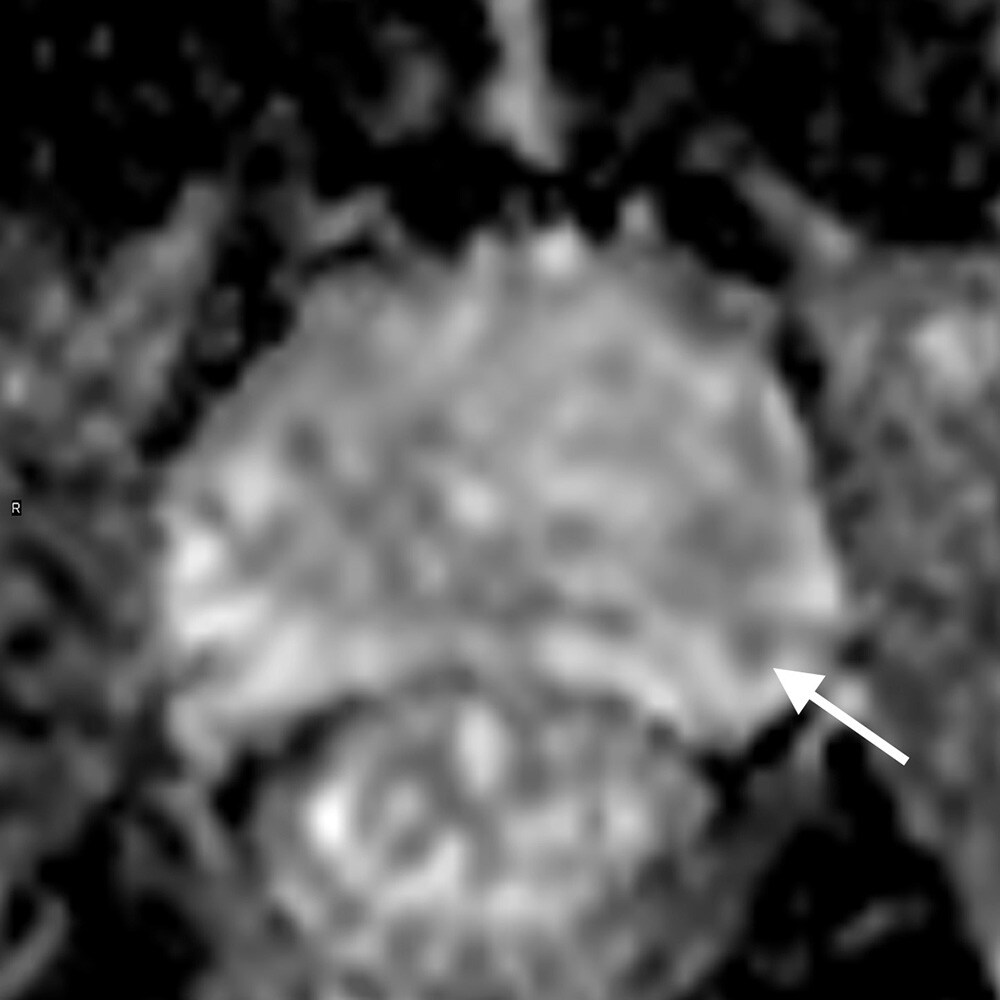

PSA高値(12.4)精査のため施行された1か月前のMRIは、直腸ガス多く、拡散強調画像で一部高信号疑うものの確証が得られなかった。そこで造影検査で再検したところ、微小なPI-RADS4病変が確認された。対象が小さいため、標的生検もふくめて見送り、経過観察している。

当該疾患の診断における造影MRIの役割

PI-RADS (prostate imaging reporting and data system)は、前立腺MRI診断の標準化として泌尿器科医にも広く知られ、前立腺癌診療に欠かせない一部となっている。PI-RADSスコアリングでは、T2強調像と拡散強調像の評価が重視され、造影は補助的な位置づけとなっている。T2強調像と拡散強調像のみを評価するbiparametric MRI (bp-mRI)の診断能が、造影を含めたmultiparametric MRI (mp-MRI)に劣らない、という報告が増え、安易にbi-MRIが多用されるきらいがある。

しかしbp-MRIは拡散強調像に負うところが大きく、拡散強調像は直腸ガスや体動、さらに撮像条件の影響で、安定した高画質を得ることが難しい。これに対し造影ダイナミック撮像は拡散強調像よりアーティファクトの影響を受けにくく、補助的、というよりは実臨床では診断の確診度を高め、フェイルセーフとしての役割が大きい。ガイドライン上も、bp-MRIで評価可能は、3テスラMRIをエキスパートが読影し、標的生検で確認できる施設でのみ、弱く推奨できるとしている。